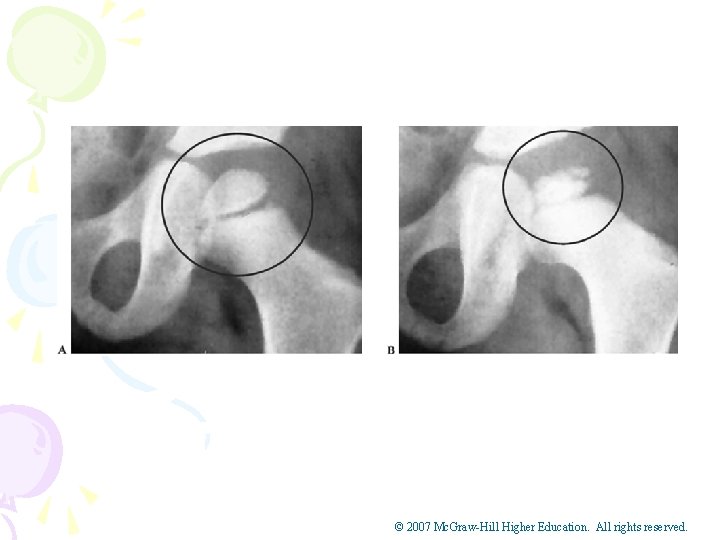

Hip Problems in Adolescent Athletes • Legg Calve’-Perthes Disease • Cause of Condition • Avascular necrosis of the femoral head in child ages 4 -10 • Articular cartilage becomes necrotic and flattens – Signs of Condition • Pain in groin that can be referred to the abdomen or knee • Limping is also typical • Varying onsets and may exhibit limited ROM © 2007 Mc. Graw-Hill Higher Education. All rights reserved.

© 2007 Mc. Graw-Hill Higher Education. All rights reserved.

• Legg-Calve’-Perthes Disease (continued) • Care – Bed rest to reduce chance of chronic condition – Brace to avoid direct weight bearing – Early treatment and head may reossify and revascularize • Complication – If not treated early, will result in illshaping and osteoarthritis in later life © 2007 Mc. Graw-Hill Higher Education. All rights reserved.

• Slipped Capital Femoral Epiphysis – Cause of Condition • May be growth hormone related • 25% of cases are seen in both hips • ___________________________________ • __________________ – Signs of Condition • Pain in groin that comes on over weeks or months • Hip and knee pain during passive and active motion; limitations of abduction, flexion, medial rotation and a limp – Management • W/ minor slippage, rest and non-weight bearing may prevent further slippage • Major displacement requires surgery • If undetected or surgery fails severe problems will result © 2007 Mc. Graw-Hill Higher Education. All rights reserved.